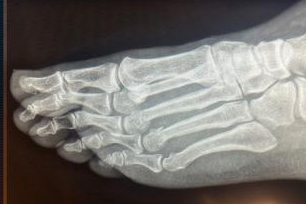

Ev kazası sonucunda ayağının kırıldığını açıklayan CHP Genel Başkanı Özgür Özel, bazı sosyal medya hesapları tarafından ortaya atılan 'ayağından vuruldu' idialarına röntgen filmleri ile yanıt verdi.

Konuya ilişkin Saygı Öztürk'e konuşan Özel, bu iddiaları FETÖ'cülerin yaydığını belirtirken, aynı zamanda röntgen filmlerini paylaşarak şu sözleri sarf etti: